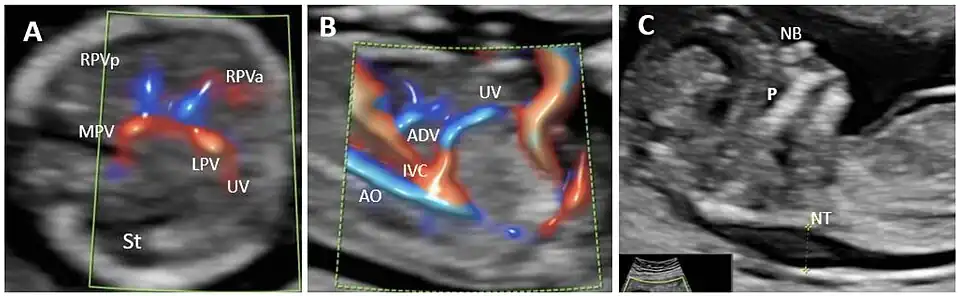

In the fetus, the ductus venosus ("DV"; Arantius' duct after Julius Caesar Aranzi[1]) shunts a portion of umbilical vein blood flow directly to the inferior vena cava.[2] Thus, it allows oxygenated blood from the placenta to bypass the liver. Compared to the 50% shunting of umbilical blood through the ductus venosus found in animal experiments, the degree of shunting in the human fetus under physiological conditions is considerably less, 30% at 20 weeks, which decreases to 18% at 32 weeks, suggesting a higher priority of the fetal liver than previously realized.[3] In conjunction with the other fetal shunts, the foramen ovale and ductus arteriosus, it plays a critical role in preferentially shunting oxygenated blood to the fetal brain. It is a part of fetal circulation.

umbilical vein left portal vein ductus venosus inferior vena cava eventually right atrium.